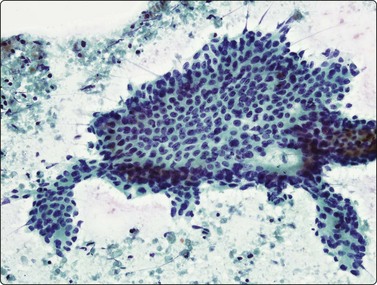

Small cell carcinoma (Figs 8.25-8.29)32,35,36,79,82,83

image

Fig. 8.25 Small cell carcinoma

Loose clusters with some dispersal and smearing artifact (Pap, HP).

Fig. 8.26 Small cell carcinoma

Pleomorphic poorly cohesive cells with little or no cytoplasm; nuclear molding (MGG, HP).

Fig. 8.27 Small cell carcinoma

Small loose cluster showing absence of cytoplasm, finely granular chromatin, inconspicuous nucleoli, nuclear molding and teardrop cells (H&E, HP).

Cytology is very successful in diagnosing small cell carcinoma in sputum and pleural fluid; in fact, sputum cytology may be more accurate than FNAC in typing this lesion. The criteria for the diagnosis of small cell carcinoma in aspirated material are similar to those in other sample types, but there are some important differences.

Cell pleomorphism is so distinctive that a diagnosis of malignancy is seldom in doubt (Figs 8.25-8.27). The most immediate impression is the absence or sparseness of cytoplasm rather than the small size of the neoplastic cell (Figs. 8.26 and 8.27). In fact, the cell nuclei may appear larger than similar cells in sputum and this may mislead one into making a diagnosis of non-small cell carcinoma. This difference in size between sputum and aspirated material is due to degenerative changes and shrinkage in sputum. It is sparseness of cytoplasm rather than size which is the most helpful initial clue in differentiating the lesion from other pulmonary carcinomas.

The combination of dispersal with clustering is also important, especially when other small cell neoplasms enter the differential diagnosis (Fig. 8.25). Lymphomas generally do not display such cell cohesion, although large fragments may be dislodged, and in some cases lymphoid cells may form clusters or packets.

Fragility of nuclei is emphasized by tear-drop cells or streaks of smeared nuclear material,226 and the close nuclear apposition and molding so commonly seen in sputum are also evident (Figs 8.26 and 8.27). Uniform coarsely granular ‘salt and pepper’ nuclear chromatin is also a well-recognized feature of this cancer in other sites, but one point of difference from sputum is the frequency of small nucleoli in aspirated material; they are less commonly seen in sputum. This may also be related to the better preservation of cells removed directly from tumor; small nucleoli are also often seen in bronchial brush material. Mitotic figures are usually easily found.